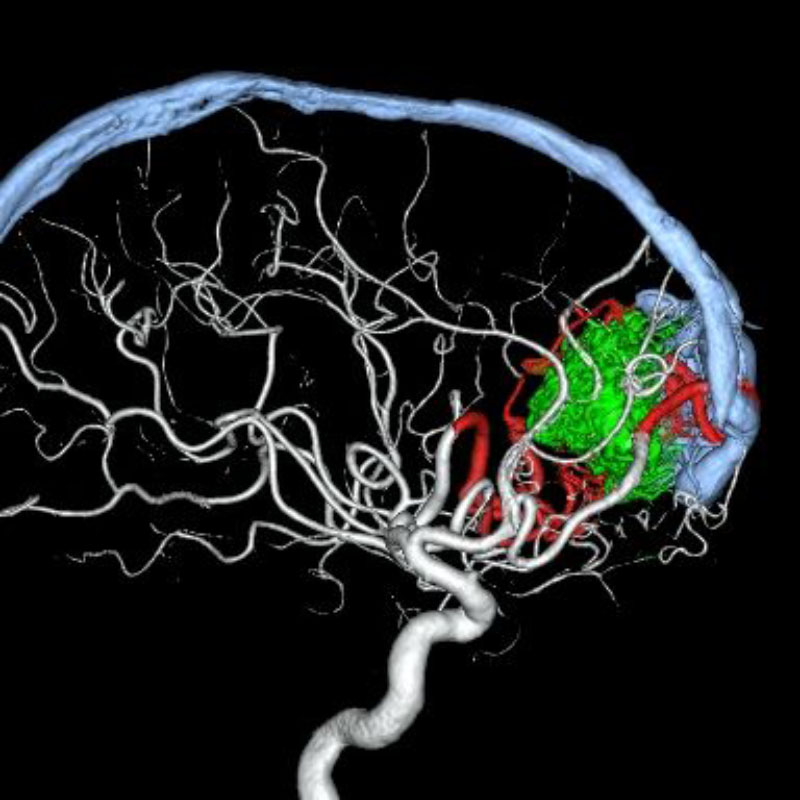

脳動静脈奇形

血管塞栓術

松田/濵田/元永